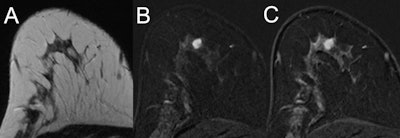

MRI of a 47-year-old high-risk patient (A, T2-weighted; B and C, subtracted early and late contrast-enhanced, T1-weighted images) shows a rather circumscribed mass lesion with heterogeneous internal enhancement and washout, corresponding to a Kaiser score of 8. Histology revealed a luminal-type invasive lobular cancer, B5b. Images courtesy of European Radiology.

MRI of a 47-year-old high-risk patient (A, T2-weighted; B and C, subtracted early and late contrast-enhanced, T1-weighted images) shows a rather circumscribed mass lesion with heterogeneous internal enhancement and washout, corresponding to a Kaiser score of 8. Histology revealed a luminal-type invasive lobular cancer, B5b. Images courtesy of European Radiology. MRI of a 39-year-old high-risk patient (A, T2-weighted; B and C, subtracted early and late contrast-enhanced, T1-weighted images) shows a circumscribed mass lesion with heterogeneous internal enhancement and persistent signal increase, corresponding to a Kaiser score of 1. Note the fibroadenoma-like T2-weighted correlate (A). Histopathology revealed a fibroadenoma, B2.